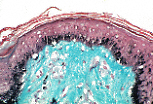

| B型角化复层扁平上皮 | ||

掌跖区以外的表皮(尤其是角质层)薄得多,角质层会解离形成絮状鳞屑。 | |

基底层的黑素细胞表现为细胞质淡染、细胞核深染的细胞。 | |

B型角化复层扁平上皮中,黑素细胞分泌黑色素并通过胞吐作用传递给邻近的角质形成细胞, 保护角质形成细胞及表皮下结构免受紫外线(U.V.)损伤。 | |

组织切片经丰塔纳银染法处理后,可在角质形成细胞和黑素细胞中均观察到黑色素。 | |

黑素细胞具有极长的指状突起,穿插于角质形成细胞之间,丰塔纳染色可显示这些突起。 | |